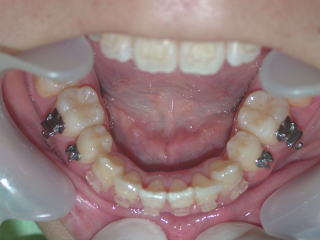

2022年7月25日初診、20代女性の叢生症例 (新潟県長岡市要町 要町歯科 歯科矯正 歯列矯正)

前歯のデコボコが気になる、とのことです。

2024年2月20日